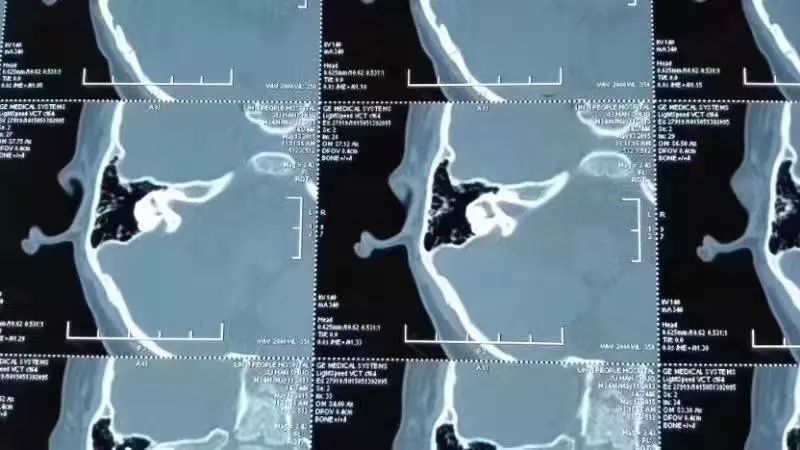

大前庭患者CT报告

4月14日跟诊大前庭门诊:"二十天中西医结合治疗大前庭效果显著"。不久前这个9岁的孩子因大前庭突发听力下降,为了能让孩子的听力回到原先水平,妈妈带着孩子不远万里从湖南邵阳赶到杭州门诊找王教授看诊。

温馨提示:大前庭病人就诊需要提前预约,并且一定要携带CT片及之前的听力检查报告!